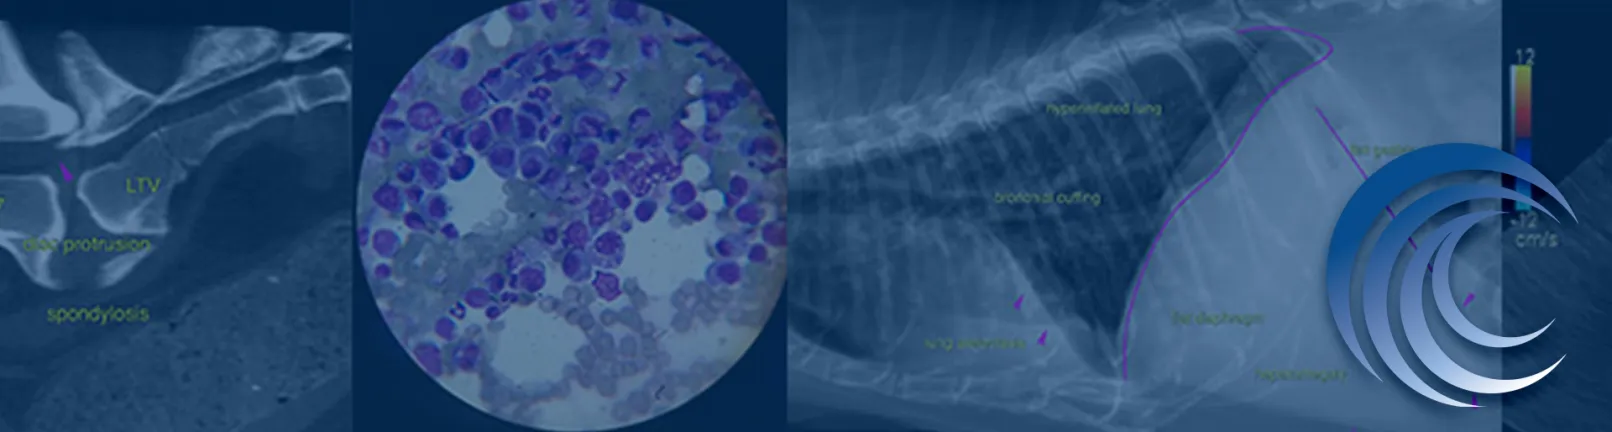

SonoPath provides remote diagnostic services for veterinarians, specializing in ultrasound and imaging. Their outdated system struggled with dynamic user management, large file handling, and complex workflows, lacking modern design and responsiveness.